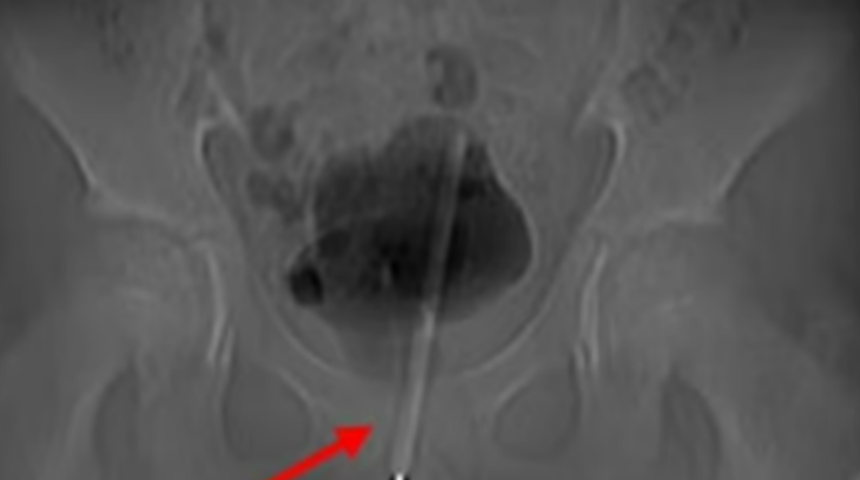

X-ışınları, termometrenin idrar yoluna sokulduğunu ve çocuğun mesanesine girdiğini ortaya çıkardı. Sağlık görevlileri, onu geldiği gibi çekmenin çocuğun organlarına zarar vereceğinden endişelendiler, bu yüzden anahtar deliği ameliyatıyla gencin mesanesinden çıkardılar.

Vakayı detaylandıran ürologlar, geldiği şekilde geri çekmek yerine mesaneden geçmeyi seçtiler. Normalde idrarı depolayan mesaneye giden dokuda küçük bir cerrahi delik açtılar ve ardından termometreyi anahtar deliğinden çekip çıkarmak için doğru açı ve konuma getirmek üzere küçük aletler yerleştirdiler. Ameliyat başarılı geçti, ancak sağlık görevlileri, çocuğun yaşadığı talihsiz olay nedeniyle uzun vadeli herhangi bir komplikasyon yaşayıp yaşamadığını ayrıntılı olarak açıklamadı.